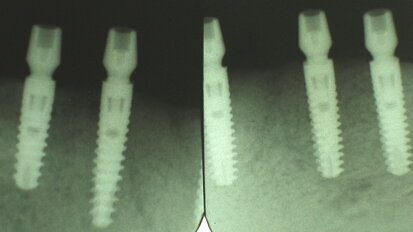

Restoring implants using lithium-disilicate,CAD/CAM fabricated restorations

Today’s consumers are always searching for the ultimate bargain, even when it comes to their dental care. They want high-quality results and minimally...